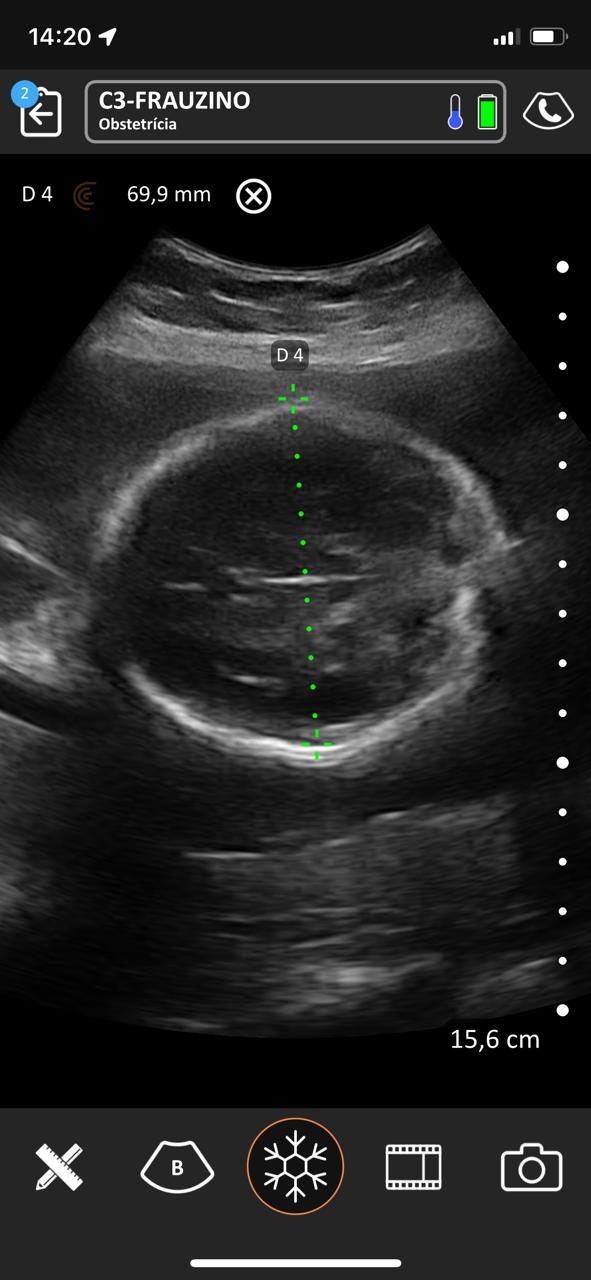

No período compreendido entre 07/03/2023 a 07/03/2025 na Estratégia de Saúde da Família São Francisco ESF-03 e Sol Nascente ESF-07 no município de Porangatu (GO), Brasil realizou-se um total de 8.349 atendimentos médicos, com 769 consultas de pré-natal e 411 ultrassons no local de atendimento de acompanhamento do pré-natal de risco habitual com aparelho portátil de bolso, sem fio, tecnologia Clarius C3 HD3, transdutor convexo, frequência de 2-6 MHz e monitores iPhone-10 e iPad Air 11. Acompanharam alguns atendimentos 12 bolsistas do PMpB dos municípios goianos Bonópolis, Britânia, Campinorte, Mara Rosa, Mundo Novo, Mutunópolis, Niquelândia, Nova Veneza, Santa Tereza de Goiás, São Miguel do Araguaia e do Pará Santana do Araguaia. Os bolsistas não tinham conhecimentos prévios sobre a PoCUS, disseram que sua formação nessa ferramenta durante o PMpB foi satisfatória e caso tivessem um aparelho sentem confiança em realizar o procedimento tanto na Unidade Básica de Saúde quanto nos domicílios, acreditaram que a formação básica recebida foi alcançada e concordam totalmente que a ultrassonografia no local de atendimento poderia estar dentro da formação especializada em medicina de família e comunidade e entenderam que no pré-natal de risco habitual é uma ferramenta que pode mudar sua conduta.

Nos acompanhamentos das consultas de pré-natal, dos 411 ultrassons realizados, 19 foram de diagnóstico gestacional e datação da idade gestacional, sendo 13 com idade gestacional menor de 14 semanas, uma na 24ª e outra na 29ª semana. Houve duas gestações gemelares que foram acompanhadas conjuntamente com o alto risco. A média de idade das gestantes foi de 26 anos e o da idade gestacional de 22 semanas e 2 dias. Os bolsistas realizaram um total de 188 ultrassons e após a familiarização teórica e prática, foram capazes de identificar 10 tópicos como situação, apresentação, dorso, batimento cardíaco fetal, movimentos fetais, órgãos internos (ao menos 1 estrutura), biometria (ao menos diâmetro biparietal e comprimento do fêmur), placenta, líquido amniótico, cordão umbilical, datar e descrever o procedimento.